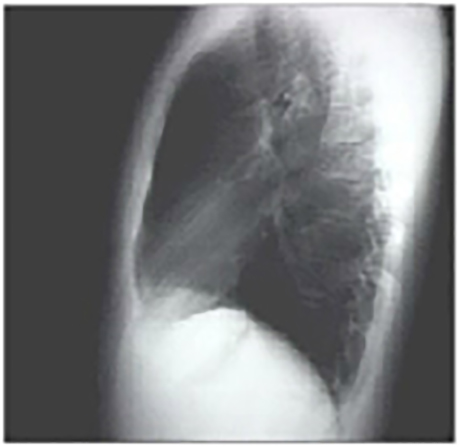

Lat

These chest X rays are normal. The PA view demonstrates no abnormalities of the bone structures, lung fields, or cardiac silhouette. The right and left heart borders are normal as are the great vessels superior to the cardiac silhouette. Note the cardiothoracic ratio is also normal, that is, it is less than 50%. The lateral view is normal, with no evidence of chamber enlargement including the normal anterior shadow of the right ventricle and posteroinferior shadow of the left ventricle.